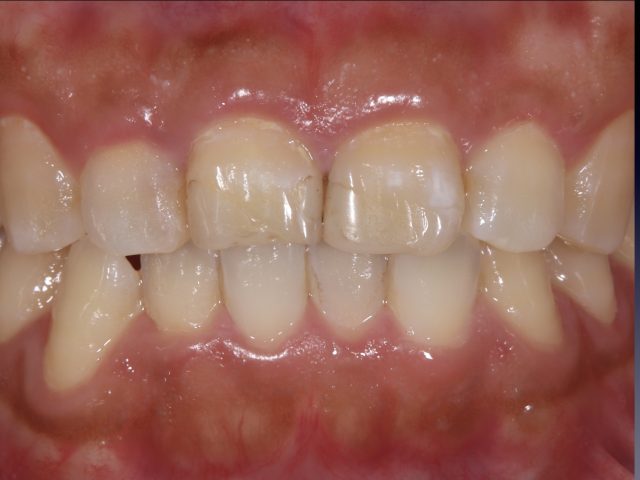

ラミネートべニアによる審美補綴治療

Before

After

| 診断名 | ラミネートベニア(1本) |

| 年齢・性別 | 20代・男性 |

| 治療期間・回数 | 2週間~3週間/2回 |

| 治療方法 | ラミネートべニアで審美修復 |

| 費用 | 132,000円(税込み) |

| デメリット・注意点 | 保険が適用できないため自費診療になる。 セラミックスインレー・クラウンに強い力がかかると割れてしまう恐れがあるため、歯ぎしりや食いしばりが癖になっている患者様にはおすすめできない場合がある |